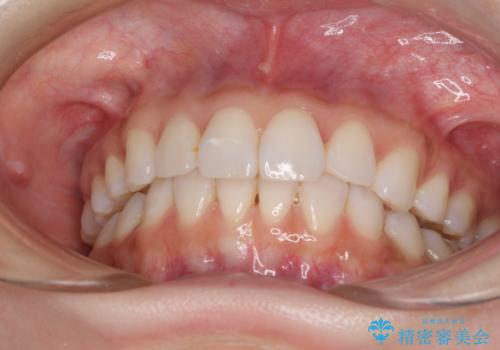

矯正治療の後戻り インビザラインによる再矯正治療

- 以前ワイヤー装置にて行った抜歯矯正の後戻りを気にして来院された患者様です。

前歯のデコボコにより、やや口元が突出した印象となっていたため、口元も引っ込めることとしました。

上下顎前歯に積極的にIPR(歯と歯の間を削る)を行い、インビザラインを用いて治療していくこととしました。

デコボコが解消されるのはもちろんのこと、突出感のあった前歯を引っ込めることができ、患者様には大変満足していただきました。